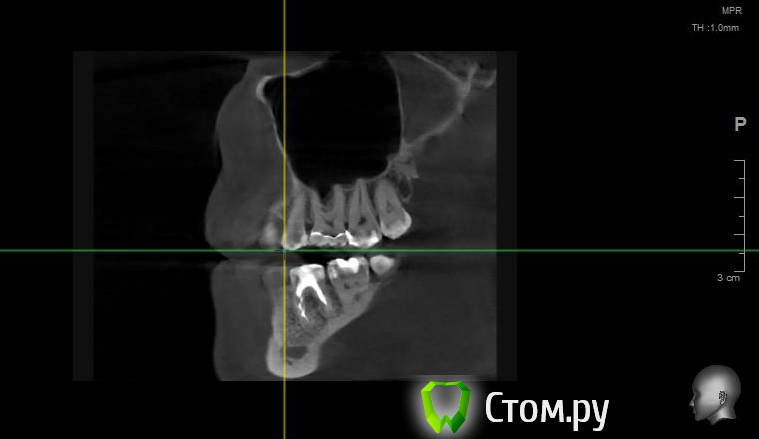

Майло Опубликовано 18 марта, 2014 Автор Поделиться Опубликовано 18 марта, 2014 (изменено) Здравствуйте, наконец сделала кт. Сегодня появилась небольшая боль над правой бровью (после лазера прошла, к вечеру появилась опять). Насморк и заложенность присутствуют. Еще сегодня опять поговорила со своим хирургом имплантологом. По симптомам сказал, что похоже присоединилась какая-то лор болячка и наверное надо сходить к лору. По кт сказал, что все нормально. Немного сужена пазуха справа, но учитывая, что я аллергичная, это нормально. Про капли типа Полидекса, сказал спросить у лора. Завтра я делаю последний лазер, по прежнему промываю нос Отривином Бэби (мне так удобней), пью кларитин, "выбиваю" нос по необходимости, но стараюсь пореже (2-3 раза в день). Еще он отдал кт через 2 недели после имплантации, на всякий случай прикреплю и этот снимок. Самый первый снимок кт был сделан через 2 недели после имплантации. Второй и третий сегодня. Подскажите, я так понимаю данное кт не показывает есть ли у меня гайморит? (к лору смогла записаться аж на 26-е) И все равно хотелось бы узнать ваше мнение по поводу состояния имплантов, есть ли там воспаление или "нагноение"? Изменено 18 марта, 2014 пользователем Майло Ссылка на комментарий

Майло Опубликовано 18 марта, 2014 Автор Поделиться Опубликовано 18 марта, 2014 (изменено) Решила еще добавить пару кадров своих пазух, вначале показалось что справа что-то есть (рис1), потом поняла это костный материал и импланты (рис2). Надеюсь так должно быть. И еще вопрос, может и "тупой", такое яркое свечение имплантов, особенно заметно на фото в профиль, это нормально? Изменено 18 марта, 2014 пользователем Майло Ссылка на комментарий

Bier Опубликовано 18 марта, 2014 Поделиться Опубликовано 18 марта, 2014 выглядит все неплохо, и пазуха чистая. Гайморита у вас нет. Сходите к ЛОРУ 2 Ссылка на комментарий

Майло Опубликовано 19 марта, 2014 Автор Поделиться Опубликовано 19 марта, 2014 (изменено) выглядит все неплохо, и пазуха чистая. Гайморита у вас нет. Сходите к ЛОРУСпасибо. А такие затемнения вокруг имплатов, это нормально? Изменено 19 марта, 2014 пользователем Майло Ссылка на комментарий

red_butler Опубликовано 19 марта, 2014 Поделиться Опубликовано 19 марта, 2014 Да, это артефакты вызванные металлом Ссылка на комментарий